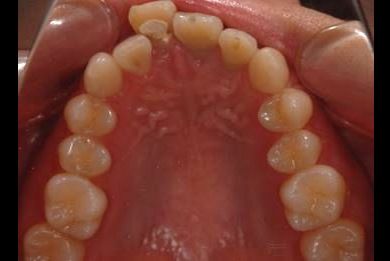

セラミックの症例写真 SHINBI

セラミック治療

| 性別/年齢 | 女性 / 20歳 | ||||||||||||||||||||||||||||||||

| 主訴 | 神経が死んで来ている歯が痛むので、治療をして欲しい。歯並びも良くできるのであればして欲しい。 | ||||||||||||||||||||||||||||||||

| 治療方針 | ジルコニアオールセラミック(クラウン1本、ブリッジ3本)、セラミック用土台2本 | ||||||||||||||||||||||||||||||||

| 総治療費 | 773,850円 | ||||||||||||||||||||||||||||||||

| 治療期間 | 5ヶ月 |